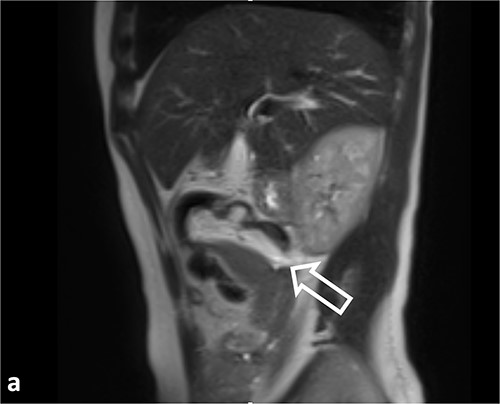

Sagittal T2WI MR images. Ileocolic intussusception (thick arrow).